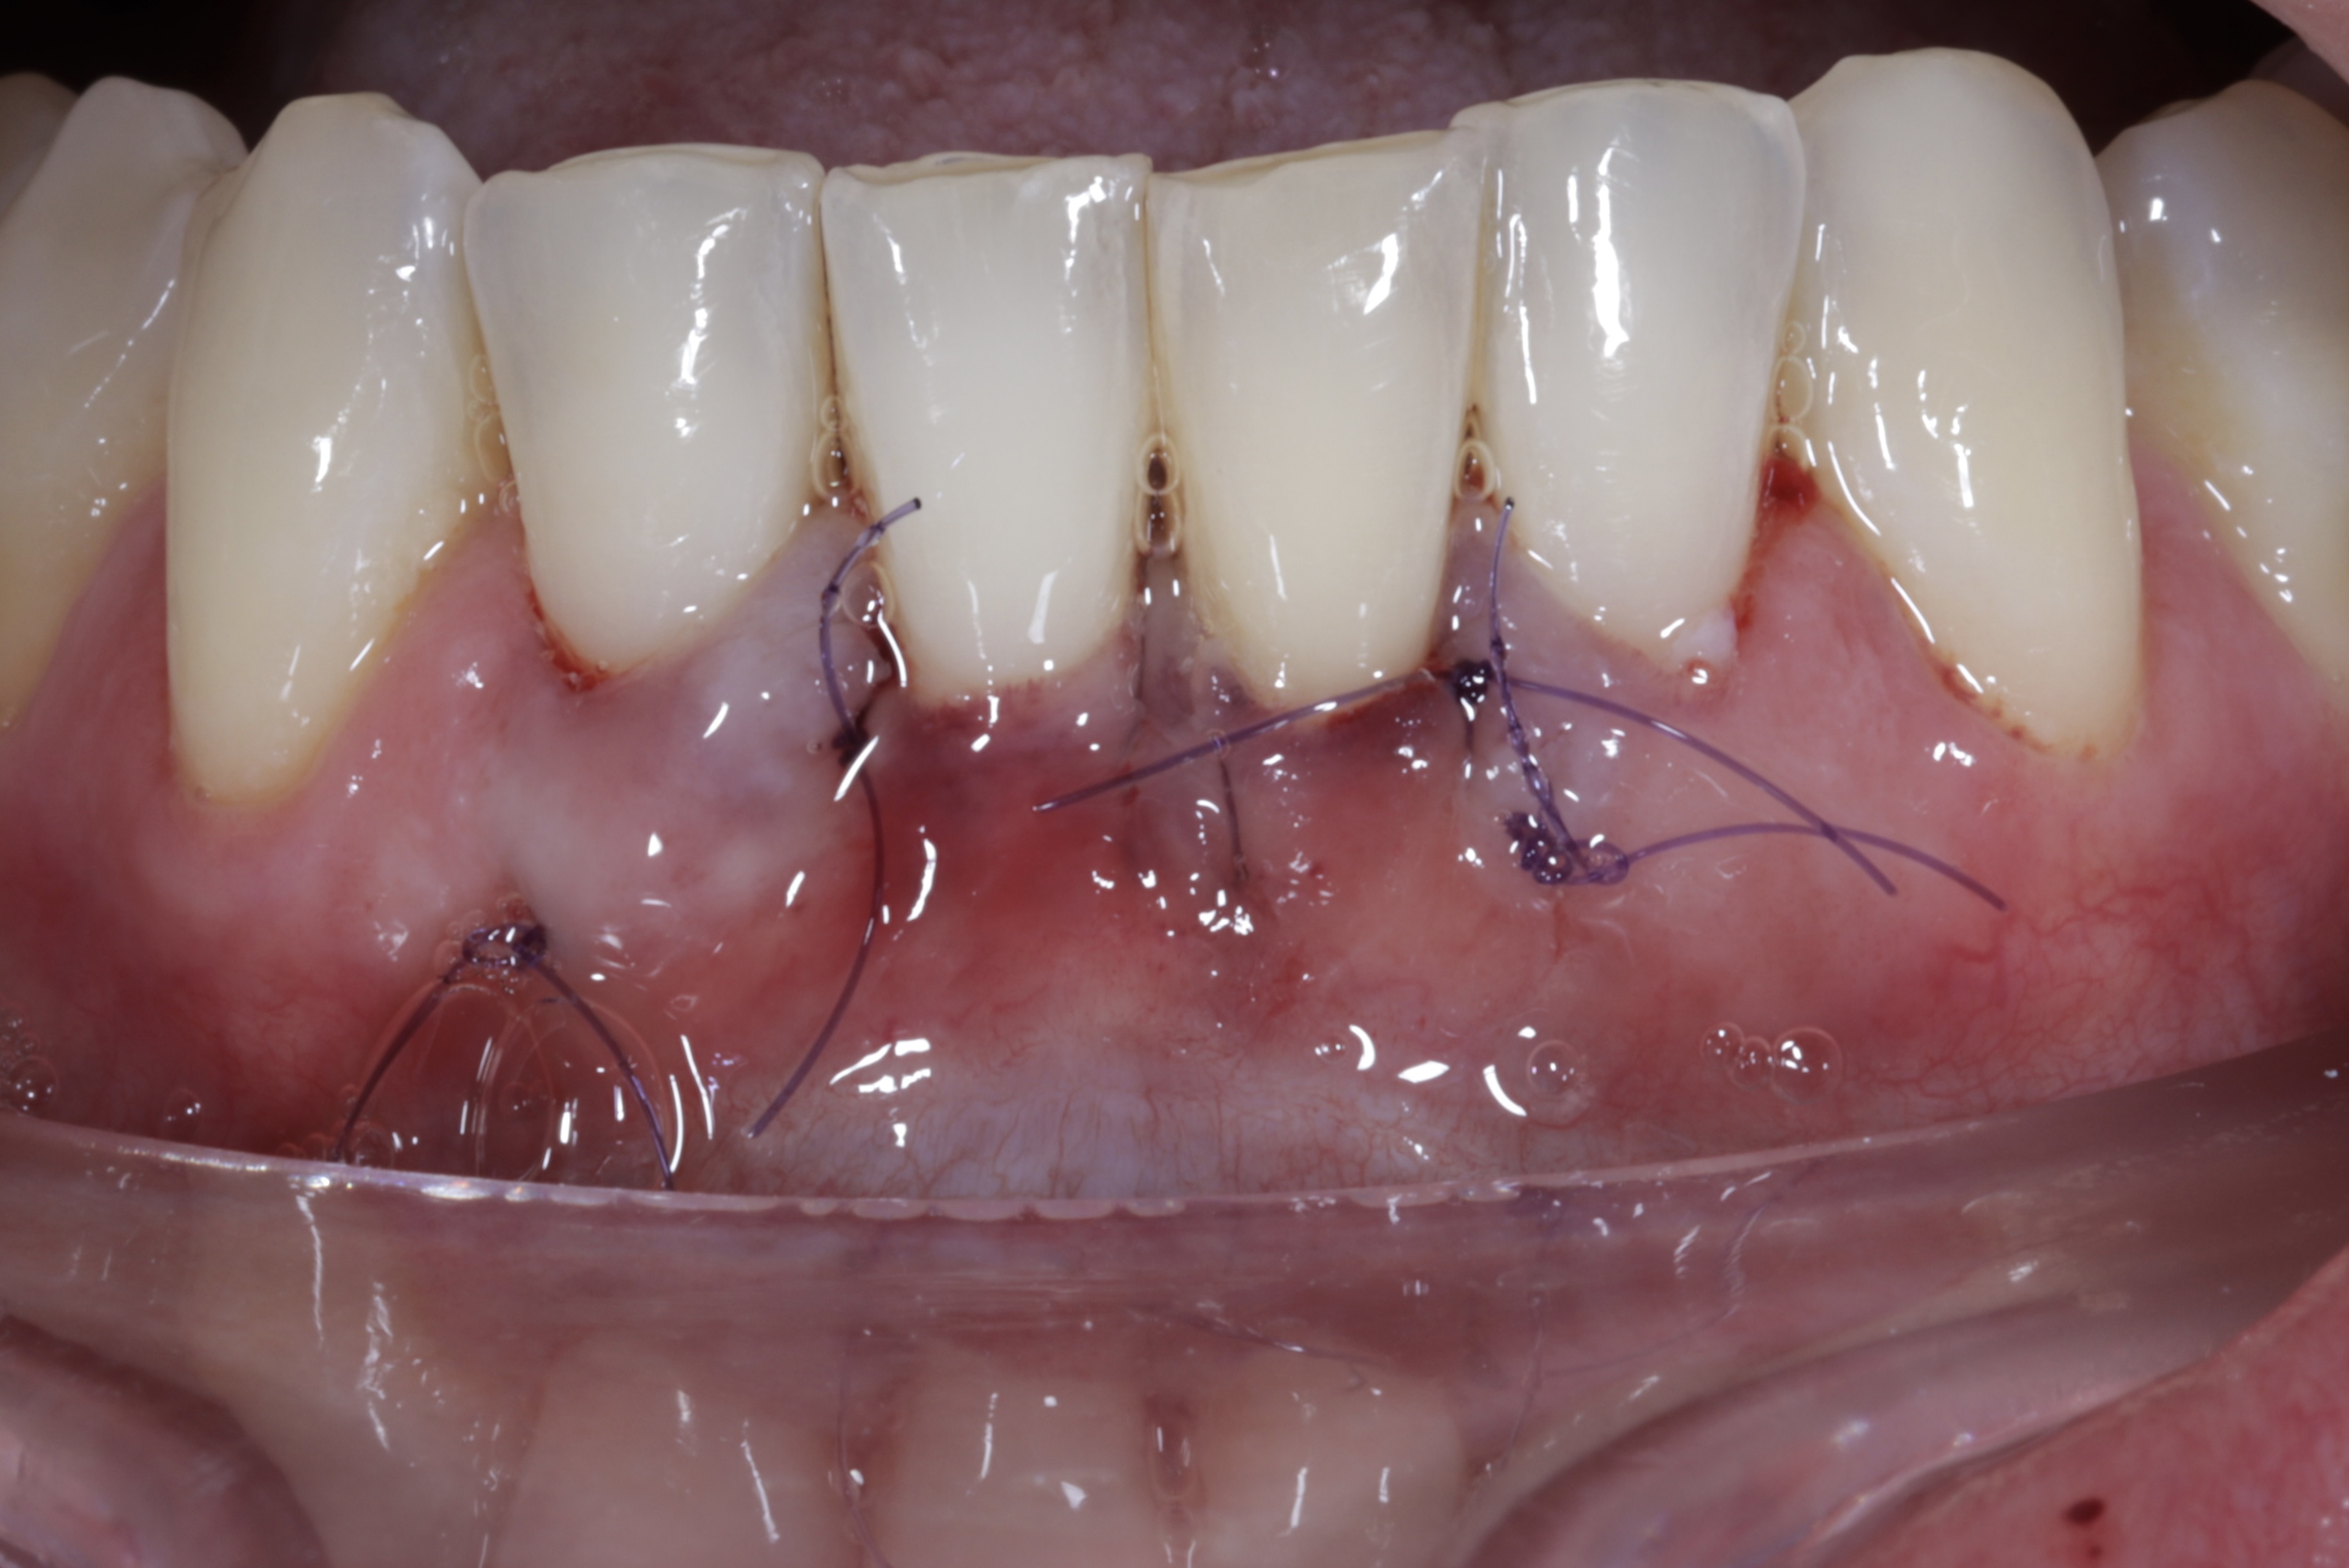

Durante una mañana, asistirás a una Cirugía Mucogingival de recubrimiento radicular de recesiones múltiples en IV y V sextante (36 a 43).

Gracias al uso del microscopio y a la proyección en tiempo real en pantalla, verás exactamente lo mismo que veo yo durante la cirugía, sin tener que estar

Podrás asistir a la planificación de casos y cirugía de injerto de tejido conectivo. Factores determinantes y elección de la técnica adecuada. Sumérgete en un protocolo predecible y técnicamente correcto para obtener resultados óptimos.

Aprende la planificación y técnica de la cirugía Mucogingival para el recubrimiento de recesiones y aumento de banda queratinizada en el sector anteroinferior

La formación comenzará con la presentación del caso clínico que se abordará durante el curso, seguida de una cirugía en directo, que permitirá observar paso a paso el procedimiento y la toma de decisiones clínicas. Durante la jornada se profundizará en los conceptos biológicos aplicados a

Una estancia clínica pensada para quienes quieran iniciarse o dar un paso más en el campo de la cirugía mucogingival. Durante esta experiencia tendrás la oportunidad de aprender en directo cómo se planifica y se lleva a cabo una cirugía mucogingival mediante técnica de Túnel.

Formación teórico-práctica completa sobre las técnicas más avanzadas en cirugía mucogingival. Durante dos días intensivos, los participantes aprenderán desde la evidencia científica y la anatomía de las zonas donantes hasta la ejecución de injertos, cubrimiento radicular y aumento de

Dos cirugías mucogingivales en directo.